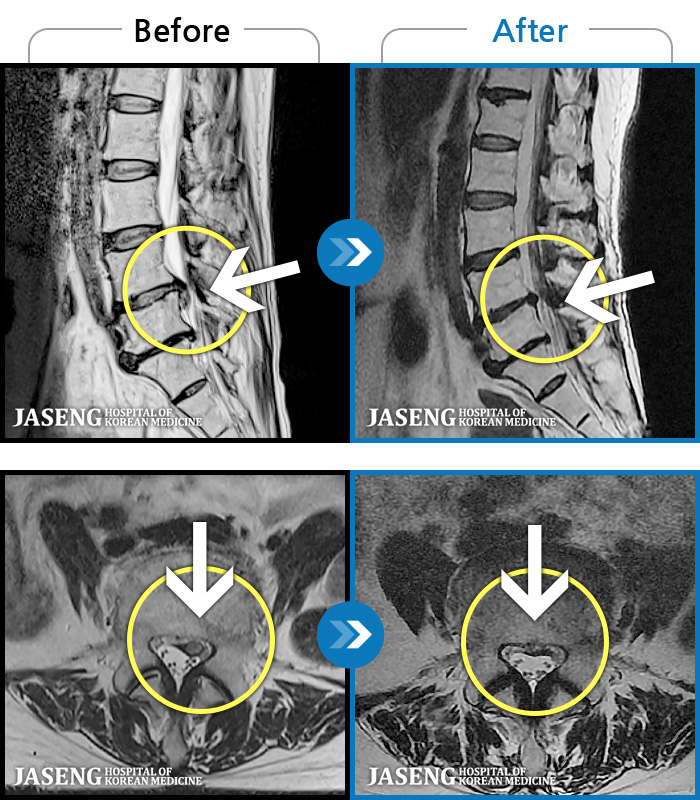

- MRI ġ

MRI ġ

MRI ũ ʸ Ȯϼ.